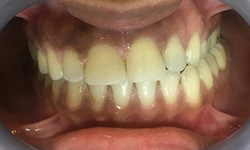

(6) Teeth Whitening

Before Treatment

After Treatment

Patient reported to us with the concern of Yellow teeth. Patient was conscious in social gatherings due to lack of confidence. Complete gum treatment and polishing was done for the patient followed by in office bleaching to achieve 2 shade whiter teeth. Home kit was a also delivered to the patient for maintenance as patient was coming from far.